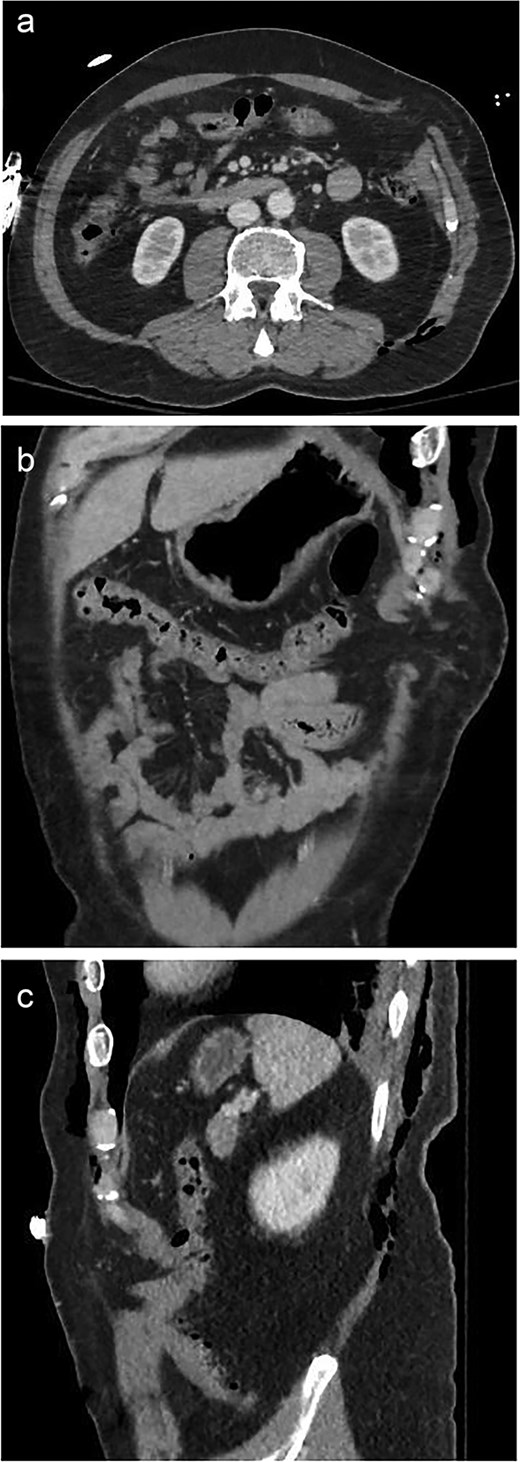

A 59-year-old male presented as a trauma activation after falling from a tree onto a fence. Primary and secondary surveys revealed paradoxical motion of the left chest, a large left-sided abdominal bulge, and degloving injury to the left lower extremity. Throughout the initial assessment, the patient was able to protect his own airway without evidence of significant respiratory distress and remained hemodynamically stable. Contrast-enhanced computed tomography (CT) of the chest, abdomen, and pelvis demonstrated comminuted and displaced left-sided rib fractures 4–11 consistent with flail chest and left fat-containing Spigelian hernia (Fig. 1).

A 59-year-old male with a traumatic Spigelian hernia seen on CT. (a) Axial, (b) coronal, and (c) sagittal views of the hernia.